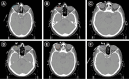

Surface mould brachytherapy is a conformal radiotherapy technique that can deliver high dose to the target while sparing nearby normal structures, Here, we aim to describe the procedurals details for high-dose rate (HDR) surface mould brachytherapy in sebaceous carcinoma of eyelid in a 54-year old lady. She was hesitant for surgery and any form of invasive intervention like interstitial brachytherapy. So, she was treated with surface mould HDR brachytherapy to a total dose of 52 Gy in 13 fractions at a dose of 4 Gy per fraction delivered twice daily using Iridium-192 isotope with no acute side effects. She was evaluated on a weekly basis for any radiation side effects and now she is disease-free for 6 months post-treatment with only mild dry eye. A detailed step-by-step procedure of surface mould technique, simulation procedure, dose prescription, planning, plan evaluation and treatment has been described in this paper. Surface mould HDR brachytherapy can be safely used as organ preserving modality of treatment for eyelid carcinoma.